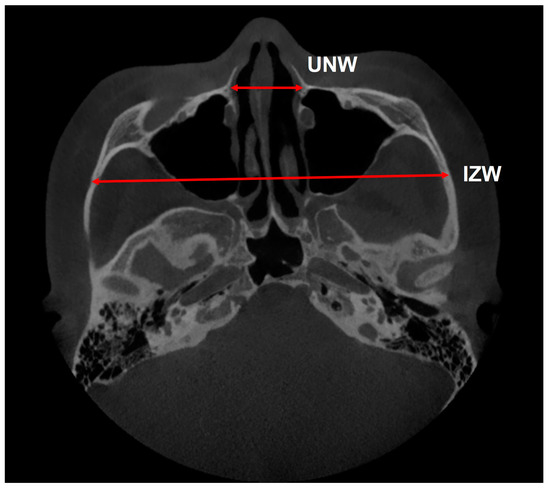

| UNW (Figure 4) | Anterior nasal width at the level of the buccal bone vertically (mm). | Measurements are taken from a slice of the zygomaticomaxillary suture in cross-section. |

| IZW (Figure 4) | Inter-zygomatic width; length of the line connecting the anterior outer points of the left and right zygomaticomaxillary sutures (mm). | |

| UNW (mm) * | 25.82 ± 3.32 | 28.22 ± 3.79 | 2.40 ± 1.19 | <0.001 *** | 0.40 | 0.27 | |

| IZW (mm) * | 122.69 ± 6.17 | 124.18 ± 6.34 | 1.49 ± 1.01 | <0.001 *** | 0.40 | 0.40 | |